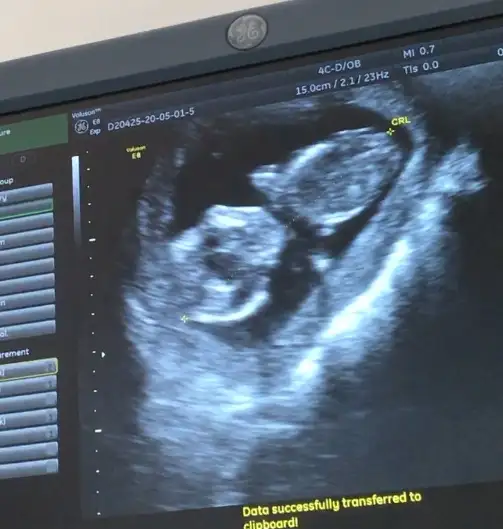

Erkek gibi 12+ yada 13 hafta olursada paylaşınMerhaba 11+3 cinsiyet tahmini alabilirmiyim bende

Erkek gibi nubu karanlık zor seçiliyor 13 haftayıda paylaşınİkra Meyra canım burada 11+6 haftalık olduk var mı bir tahmin nin

Ben de seni takip ederken biraz öğrendim ultrasonda izlerken bana da erkek gibi geldi ama doktor kıza benziyor kesin değil dediErkek gibi nubu karanlık zor seçiliyor 13 haftayıda paylaşın

Nubu karanlık zor seçiliyor 13 haftayı paylaşın dedim canımBen de seni takip ederken biraz öğrendim ultrasonda izlerken bana da erkek gibi geldi ama doktor kıza benziyor kesin değil dedi